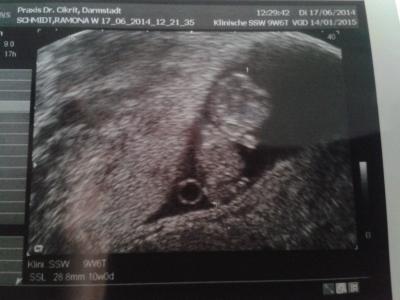

Meinem Gummibärchen geht's super. Herzschlag kräftig, gezappelt ohne ende, 3cm bis zum steiß und soooooo süß! Es hat sogar am Daumen genuckelt! Bin immer so viel beruhigter wenn ich beim FA war. Freu mich schon aufs nächste mal. Wie geht's euch so?

Bild zu yay.... 11. ssw , zurück vom FA - Forum für Januar - Mamis